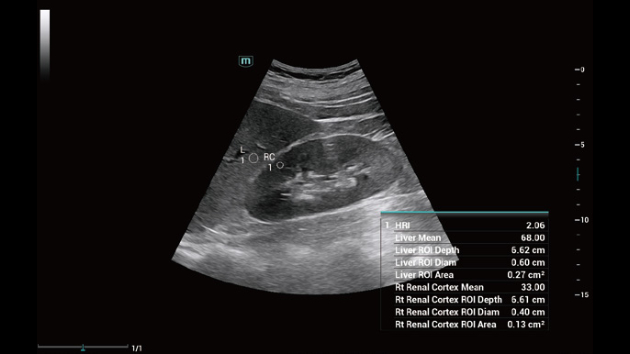

Comprehensive Imaging Solutions Powered by ZST+

The ZST+ platform is an extraordinary innovation, representing an ultrasound evolution. Transforming ultrasound metrics from conventional beam-forming to channel data based processing. It overcomes the traditional trade-off limitation among spatial resolution, temporal resolution and tissue uniformity, delivering exceptional image quality for infinite imaging solutions with non-stop improvements.